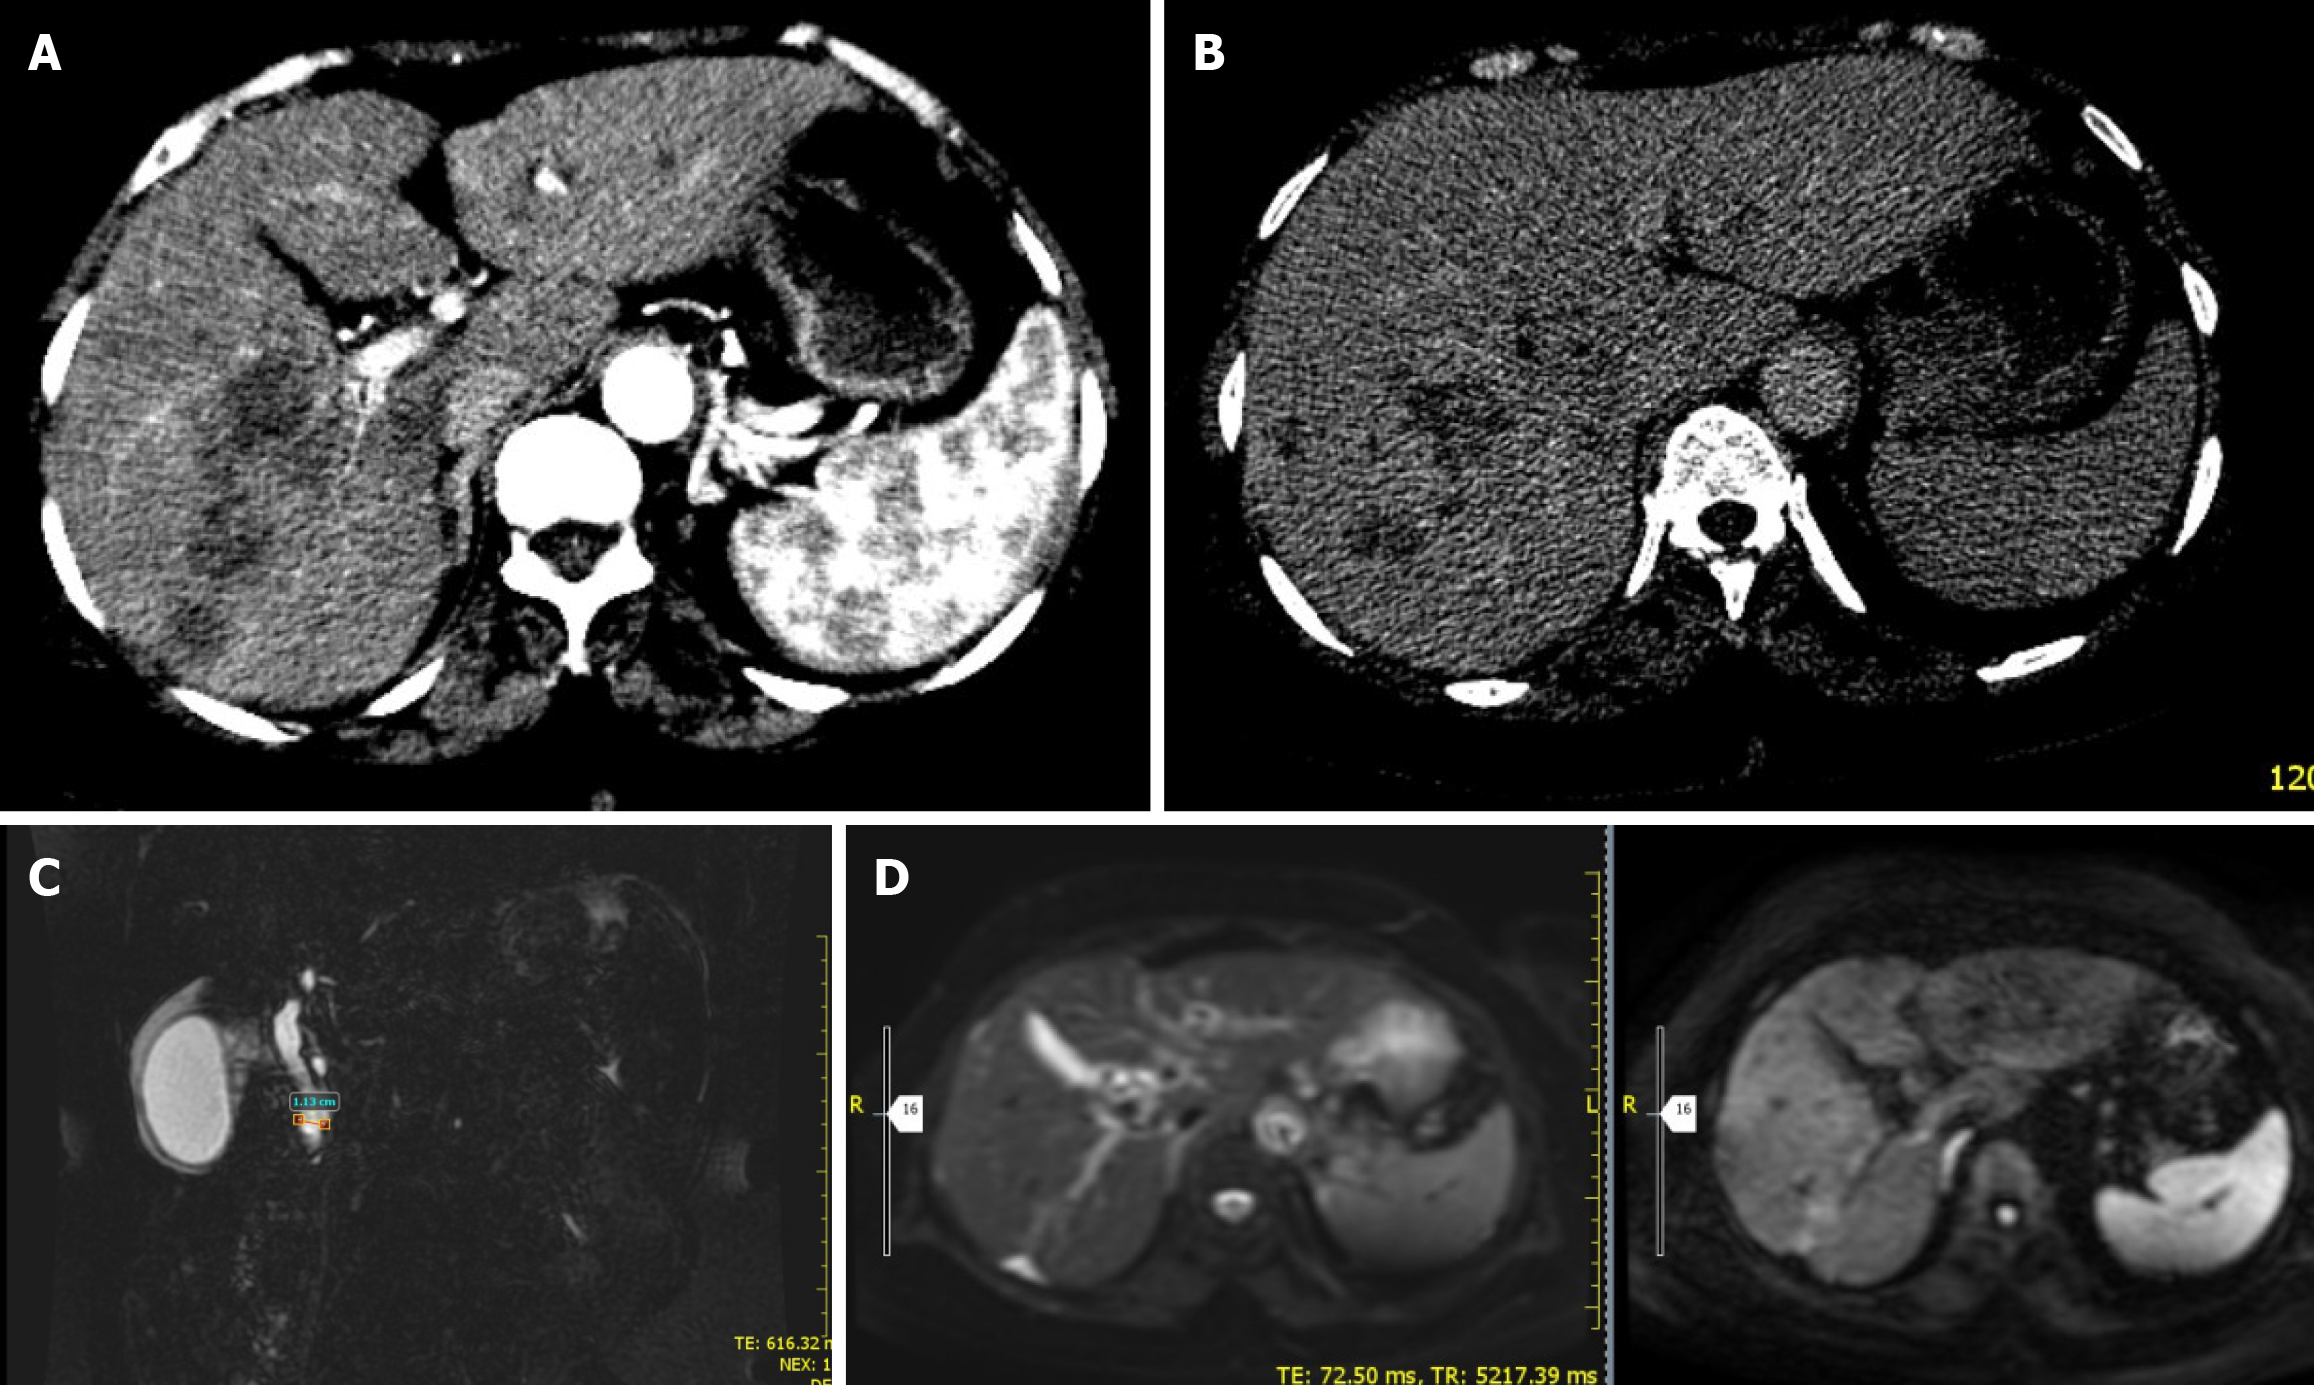

Figure 5 Abdominal computed tomography, magnetic resonance imaging, and magnetic resonance cholangiopancreatography images.

A and B: Shows arterial phase axial abdominal computed tomography (CT) can showing ill defined, confluent hypodense right lobe liver lesions (A). Delayed phase abdominal axial CT scan showing progressive central enhancement of the right lobe hypodense lesion (B); C: Showing dilated complete blood count and edematous gallbladder wall; D: Abdominal magnetic resonance imaging diffusion weighted imaging and apparent diffusion coefficient image showing focal right lobe capsular retraction with adjacent mildly restricting right lobe liver lesion.